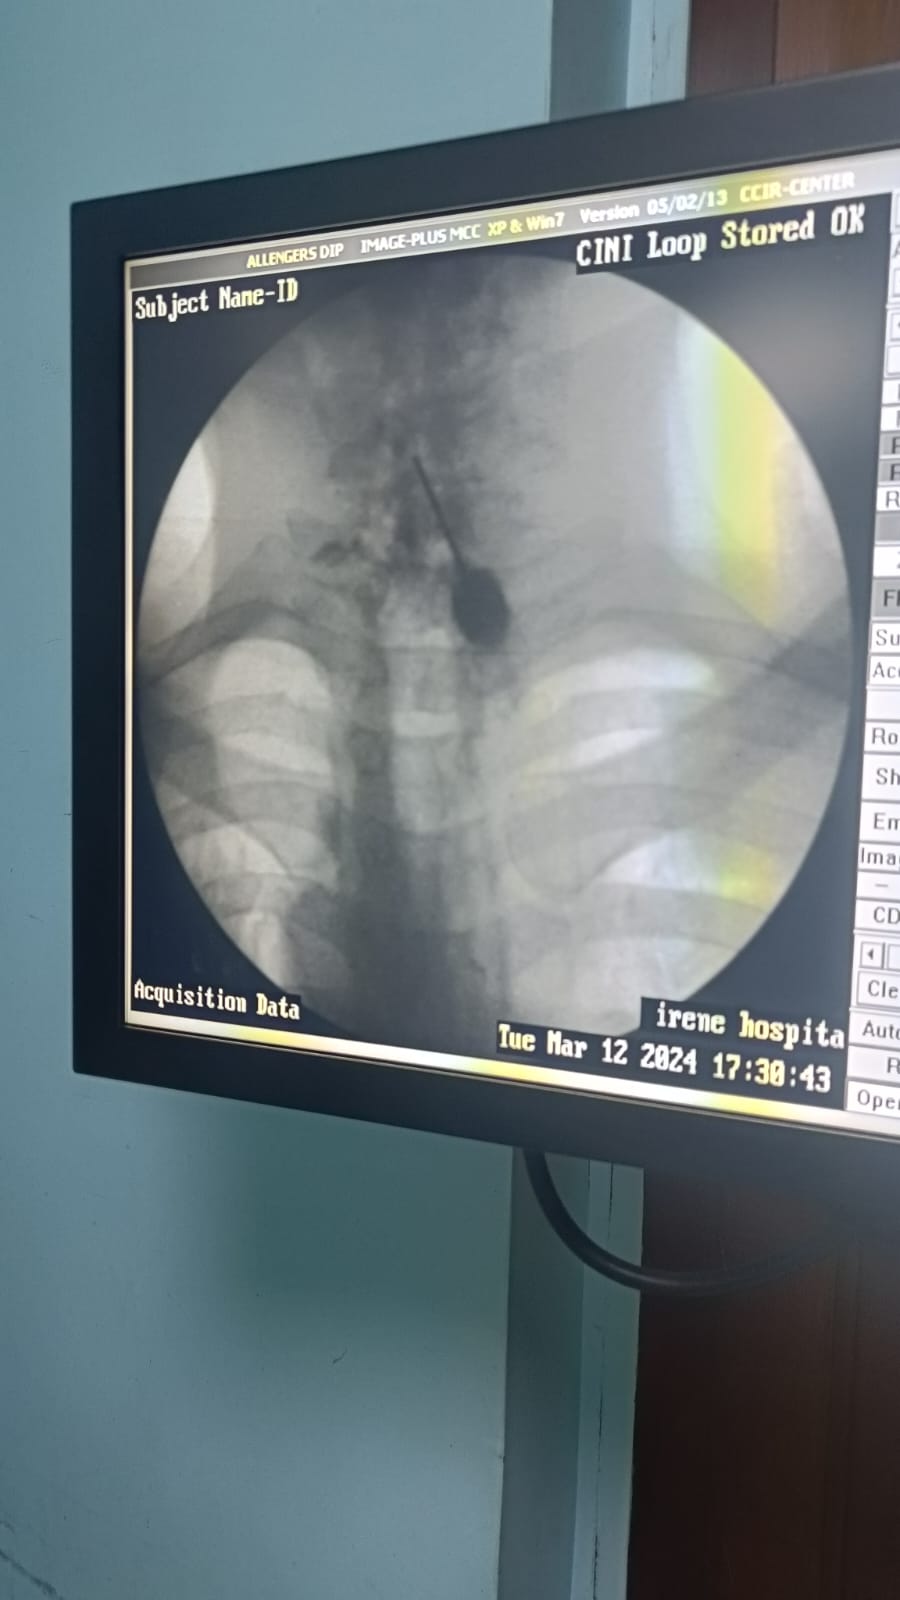

- Therapeutic Procedures: In some cases, therapeutic procedures such as injections, nerve blocks, or physical therapy may be recommended to target the underlying cause of the pain and provide relief.